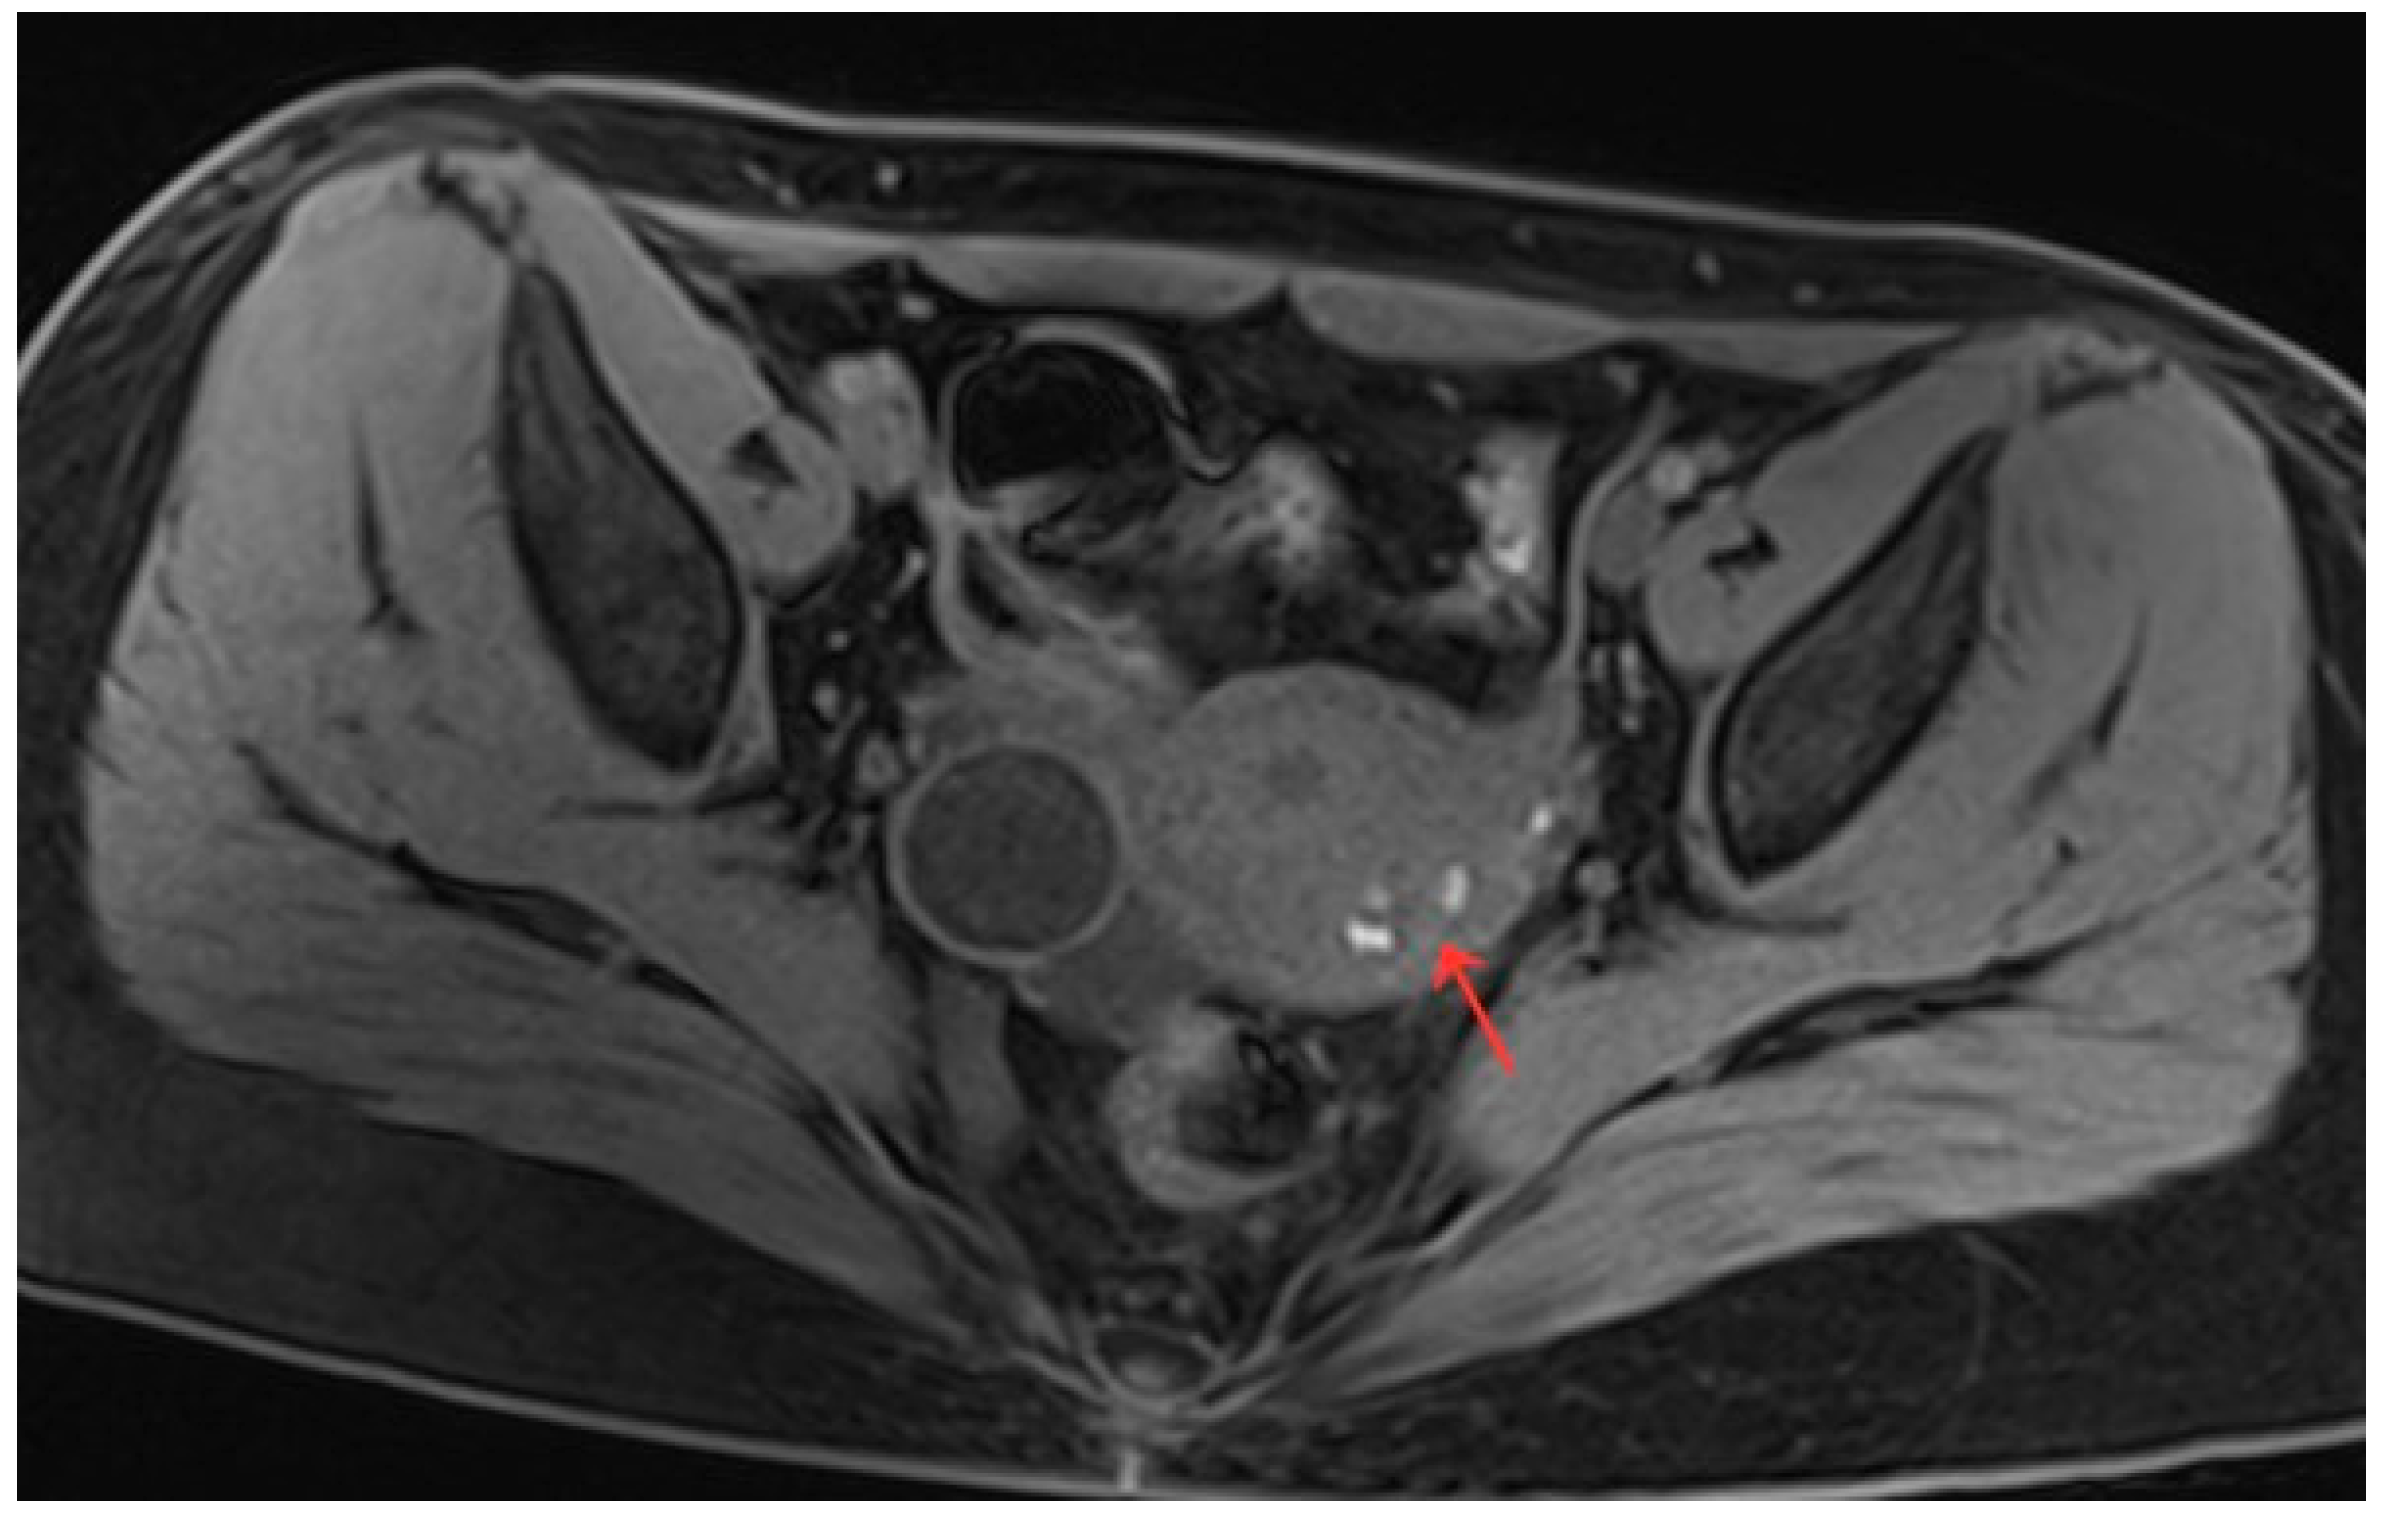

Figure 6.

Pelvic MRI shows lesions after HIFU treatment (1st day) (red arrow).